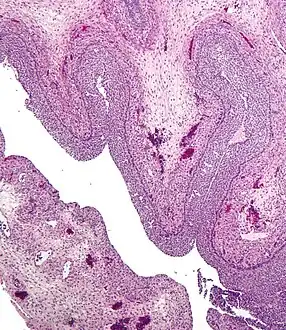

Human ovary with fully developed corpus luteum

Luteinized follicular cyst. H&E stain.